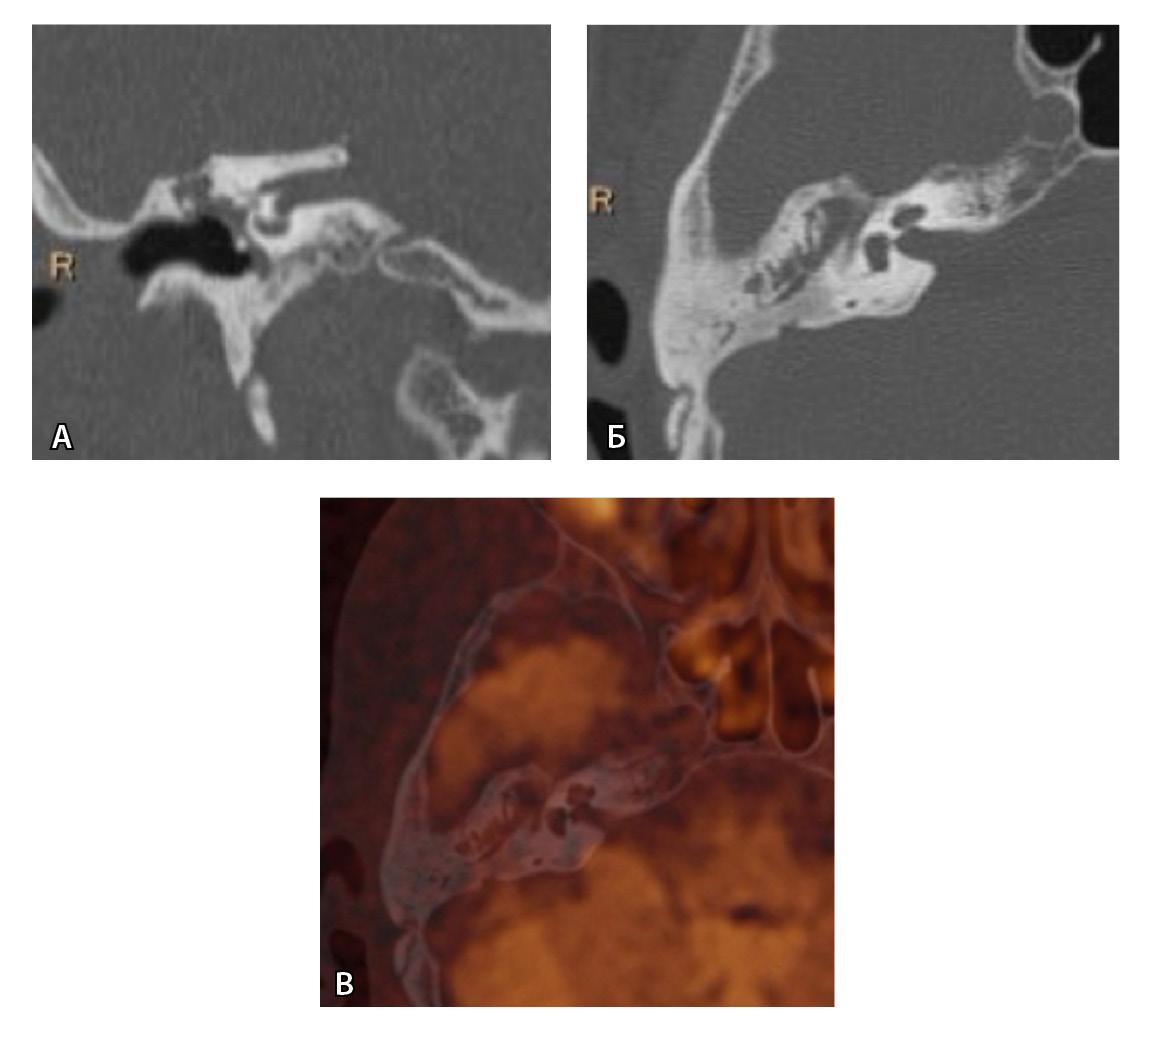

Рис. 3. Хронический правосторонний средний отит. По данным компьютерной томографии (А, Б) нет ремоделирования барабанной полости, деструкции и смещения косточек, скутум сохранен, данных за холестеатому нет. При магнитно-резонансной томографии (В, Г) у того же пациента выявлен очаг высокого магнитно-резонансного сигнала, который при слиянии локализовался в области пространства Пруссака. Заключение и интраоперационно – холестеатома пространства Пруссака